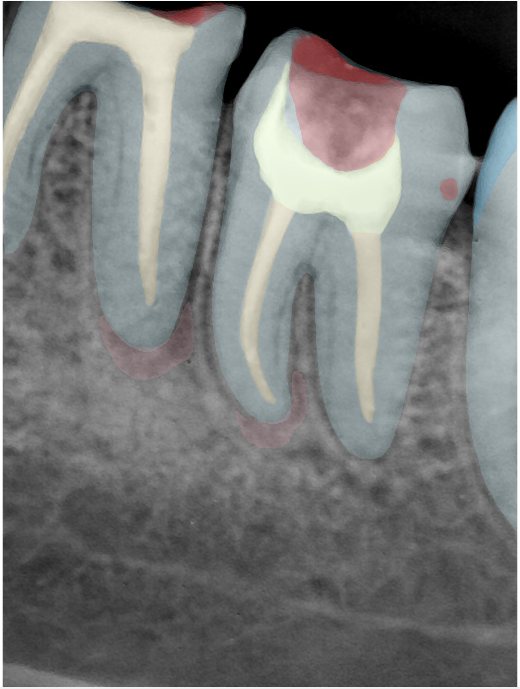

CR/DR 牙齿分割阶段记录

当前进展

- 完成了 CR/DR 牙齿相关分割训练

- 当前结果已经达到阶段预期,但仍有细节问题需要继续处理

相关测试

遇到的问题

- 训练过程中出现过 mask 下移问题

- 部分结果会出现 box 填充异常

- mask 边缘仍然有比较明显的锯齿感

第二版算法问题测试